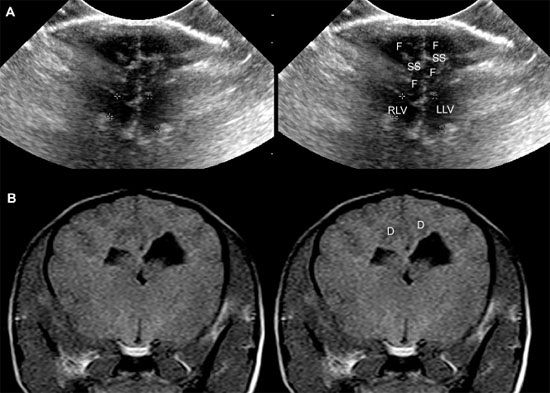

The sonographic anatomy of the brain of normal dogs has been described (Hudson et al. 1989) (Figure 1.3). The longitudinal fissure and splenial sulci form a hyperechoic umbrella-like structure that can be used as a landmark to locate the midline of the brain. This is particularly useful when a natural or created defect in the skull is located asymmetrically. The cingulate gyrus is found deep to each splenial sulcus. Rostrally, the caudate nuclei are recognizable as hyperechoic curved structures. The lateral ventricles are located medial to the caudate nuclei and vary greatly in size according to the breed, age, and individual. Asymmetry is common. Cerebrospinal fluid (CSF) is anechoic and may cause the lateral ventricles to appear as small anechoic slits in some individuals.

Figure 1.3. Transverse sonograms of the brain of a 1-month-old Yorkshire terrier. The ventricles are asymmetrical but within normal limits. A: Rostral sonogram. B: Sonogram at the level of the interthalamic adhesion. C: Sonogram at the level of the third ventricle. D: Sonogram with the ultrasound beam angled caudally to image the mesencephalon. E: Sonogram with the ultrasound beam angled caudally to image the cerebellum. 3, third ventricle; CC, corpus callosum; CG, cingulate gyrus; CN, caudate nucleus; F, fornix; H, hippocampus; IA, interthalamic adhesion; LF, longitudinal fissure; LLV, left lateral ventricle; M, mesencephalon; P, pyriform lobe; Po, pons; RLV, right lateral ventricle; SS, splenial sulcus; Su, subarachnoid space; T, thalamus; and V, vermis.

As the beam is swept slightly more caudally, the rostral fornix comes into view. Choroid plexus is hyperechoic while it lies on the floor of the central portion of the lateral ventricle and the roof of the temporal horn. It may be difficult to distinguish between the caudate nucleus and the adjacent choroid plexus in the lateral ventricle, so only a single hyperechoic focus might be seen on each side of the midline in some dogs. If there is sufficient CSF, the lateral ventricle can be seen.

In older puppies and adult dogs, alternating hyperechoic and hypoechoic lines represent the callosal sulcus, corpus callosum, and fornix. Comparison with histological samples suggests that the most superficial hyperechoic layer is the callosal sulcus, which contains vessels that pulsate. The corpus callosum is comprised of a hypoechoic surface with a deeper hyperechoic border. The fornix is hypoechoic. In the first few days of life, these structures may appear only as a single hyperechoic region. Detail improves as myelination progresses after birth. Most of the brain is uniformly hypoechoic, but the pyriform lobes are visible because of hyperechoic meninges dorsal to each lobe.

When the probe is tilted to sweep the ultrasound beam caudally, the dorsal portion of each hippocampus appears as a hypoechoic structure close to the midline. Dorsolateral to each of these structures, a hyperechoic area represents choroid plexus in each lateral ventricle. Another hyperechoic area is seen in the midline ventral to the level of the dorsal portions of the hippocampi. Depending on the angle of ultrasound section, this hyperechoic area may represent choroid plexus in the dorsal portion of the third ventricle or pia mater that is located more caudally in the adjacent subarachnoid space. Vessels and trabeculae in the subarachnoid space may create a complex of echoes that outline the mesencephalon and cause it to appear as a dome-shaped hypoechoic structure. The petrous temporal bones will create irregular hyperechoic echoes on the floor of the cranium on each side of the midline deep to the hypoechoic pyriform lobes.

More caudally, the osseous tentorium is a hyperechoic structure shaped like an inverted V. In older animals, this structure often prevents visualization of the caudal brain, but the medulla and cerebellum can be imaged in neonatal animals. The medulla is hypoechoic. The vermis of the cerebellum is represented by a stack of hyperechoic lines seen in the midline. Each lateral cerebellar hemisphere is located more laterally as a hypoechoic structure.